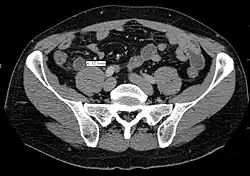

Компьютерная томография информативна при наличии спирального томографа, когда выявляется обтурация червеобразного отростка, расширение его просвета, утолщение стенки (> 1 мм) признаки свободной жидкости (воспалительного выпота) в брюшной полости.